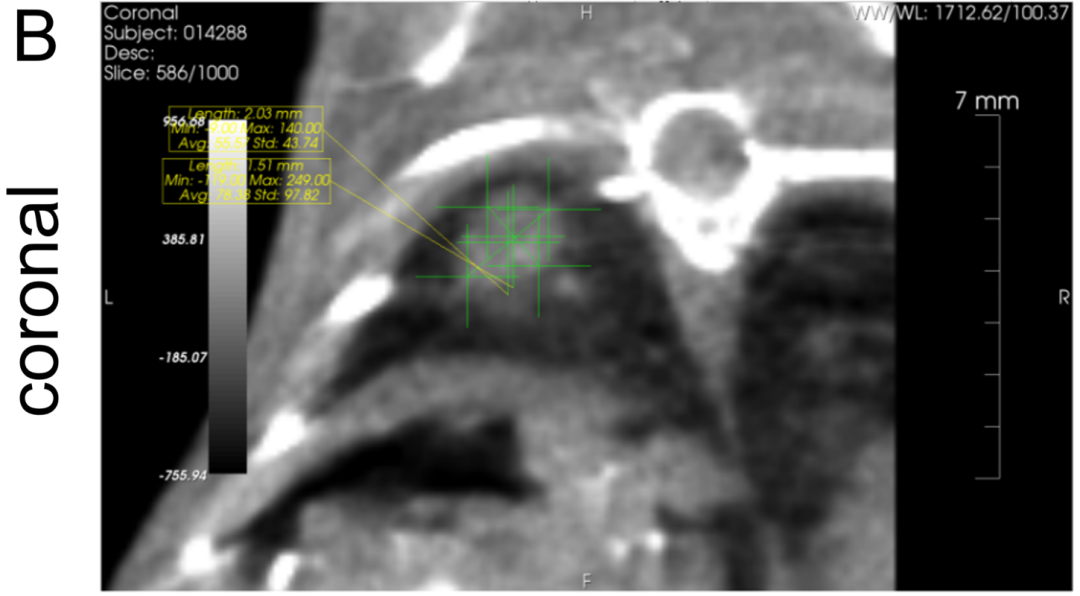

(A)横截面; (B)冠状面;(C)矢状面;CT扫描三个截面中最大的直径用于后续药效评价典型图示。